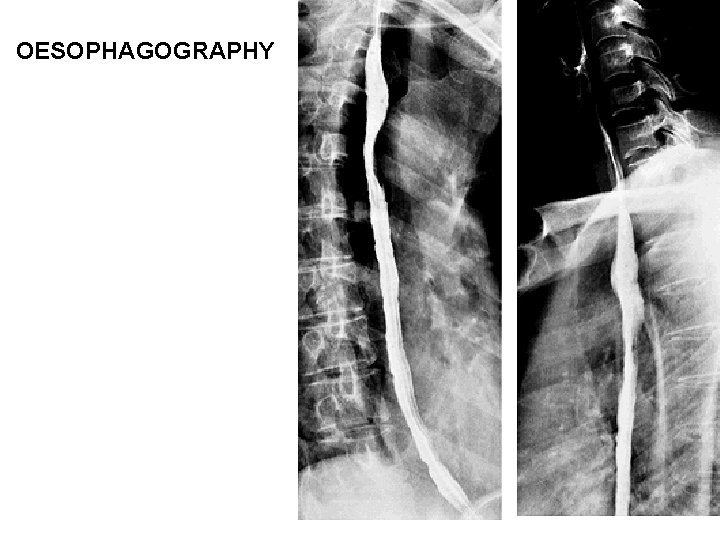

OESOPHAGOGRAPHY